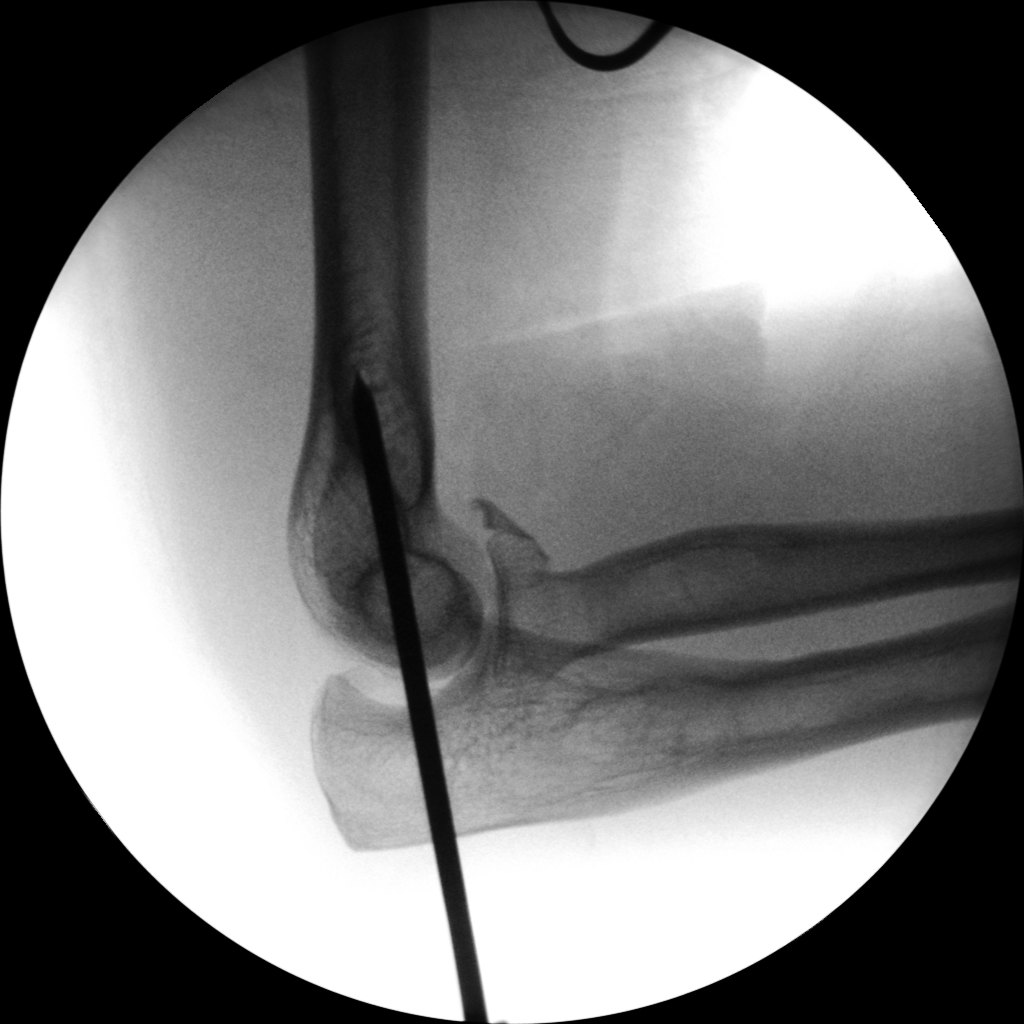

CRIF - Closed reduction internal fixation

ORIF - Open reduction internal fixation

Clinical Evidence

Skan-C is a great C-arm for orthopaedic treatments for several reasons